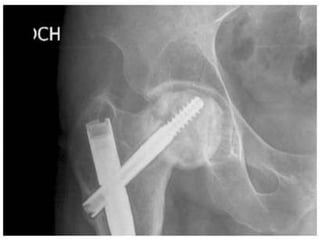

• Screw cut out – mainly following incorrect

• Screw cutout – mainly following incorrect placement of screws